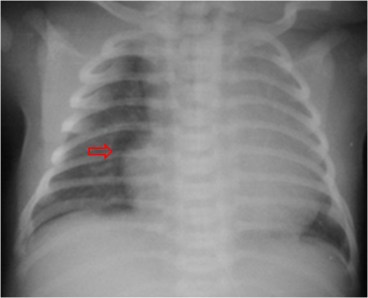

SIGNO DE LA BANDA MEDIAL

Signo de neumotórax de disposición medial en la radiografía de tórax. Consiste en la presencia de una banda de baja densidad (flecha) que recorre el hemitórax correspondiente pegado a la silueta cardiomediastínica. A diferencia del neumomediastino, a menudo llega a las porciones inferiores de la silueta cardíaca, y es unilateral. El neumopericardio puede distinguirse porque el aire rodea la silueta cardíaca y limitado por el pericardio.

Aunque fue descrito como signo de neumotórax en el neonato, puede encontrarse también en el adulto.

Otro ejemplo, en un adulto. La flecha verde indica la banda medial mientras que la flecha naranja señala el neumotórax en posición lateral.